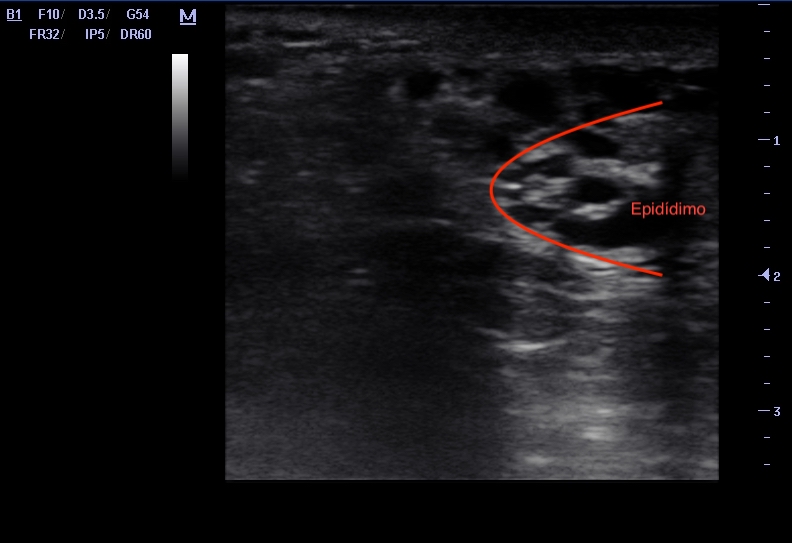

Se observa una imagen hiperecoica en 1/3 medio pared anterior de testículo derecho compatible con calcificación que deja sombra posterior, bien delimitada y sin imagen adyacente hipoecoica ni heterogénea. Además, se observa imagen en panal de abeja en epidídimo, que sugiere ectasia tubular de rete testis.